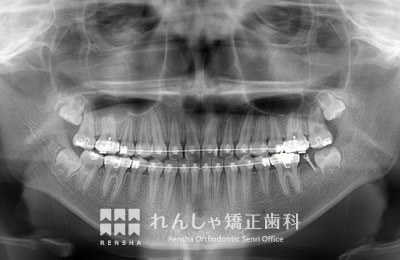

中高生

永久歯列はほぼ完成してしますが、歯列を側方だけでなく後方へも拡大し、埋まっていた右上奥歯を引っ張り出しています。

| 主訴 | 埋まったままでてこない歯がある |

|---|---|

| 診断名 | Angle Class II 小臼歯の埋伏と叢生を伴う上顎前突 |

| 初診時年齢 | 13歳5か月 |

| 装置名 | マルチブラケット装置 |

| 抜歯非抜歯 | 非抜歯 |

| 治療期間 | 2年3か月 |

| 費用の目安 | 約82万円+消費税(検査料金、都度の処置費用等も合わせた総額) |

| リスク副作用 | 歯の移動に伴う軽微な歯根吸収、歯槽骨吸収、歯肉退縮(本症例では軽度の歯根吸収を認めた)、矯正器具装着中のカリエスリスク増大(本症例ではカリエス発生無し) |